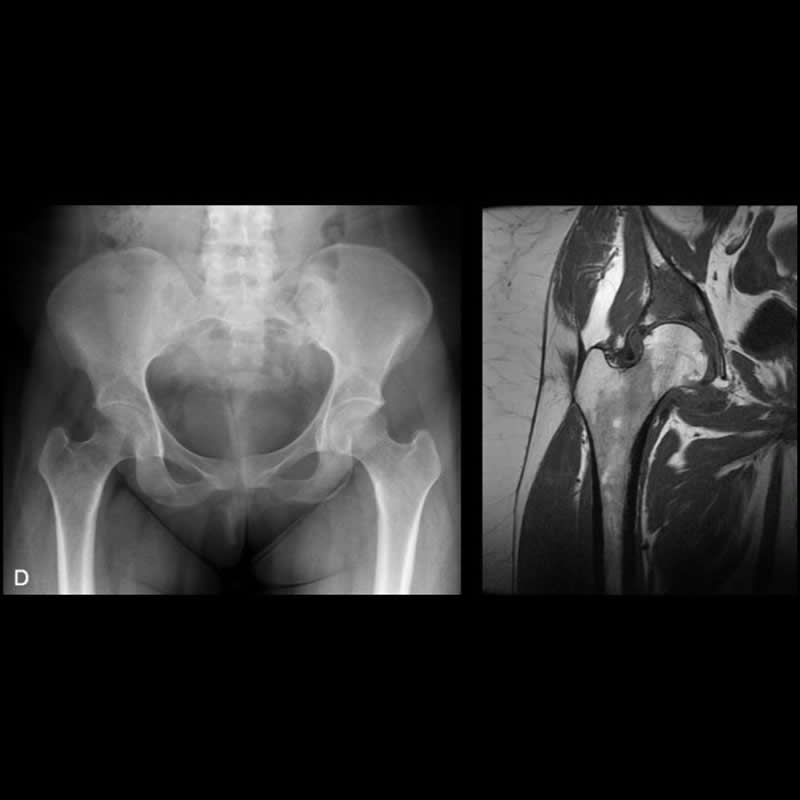

Agosto 2021. Sanatorio Allende Mujer de 28 años con coxalgia derecha progresiva de un año de evolución.